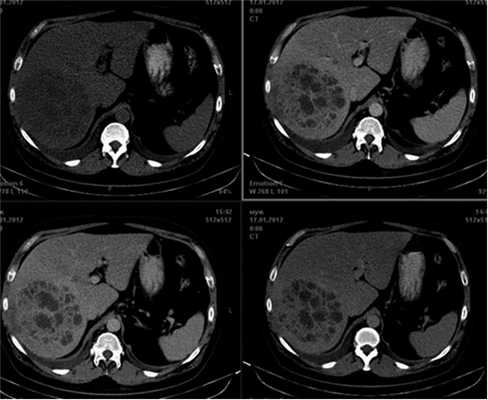

97 ЕД/мл (норма менее 37). Уровень билирубина - 90 мкмоль/л. При спиральной КТ с контрастным усилением (рис. 1) Рисунок 1. Компьютерная томограмма печени у пациента с псевдоопухолью. заподозрен гепатоцеллюлярный рак с внутриорганным метастатическим поражением и двухсторонний экссудативный плеврит. При последующей плевральной пункции было эвакуировано 1500 мл транссудата, не содержащее по данным цитологического обследования опухолевых клеток.

В VI-VII сегментах печени определяется объемное образование с нечеткими, волнистыми контурами, неоднородной структуры, в центре имеются неправильной формы участки с жидкостными характеристиками. Окружающая паренхима с признаками инфильтративных изменений. По верхнему контуру образования прослеживается дугообразно деформированная ветвь правой печеночной вены, по переднему контуру - смещенная ветвь средней печеночной вены (рис. 2). Рисунок 2. Магнитно-резонансная томограмма органов брюшной полости без контрастного усиления. В правой доле печени — опухолевый узел округлой формы гетерогенной структуры с неровными контурами. Наиболее отчетливо визуализируется в импульсной последовательности STIR.